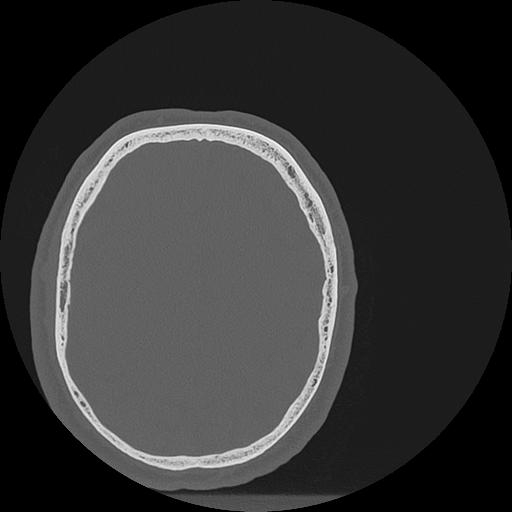

7 HUESO,,Vol,0.5,HUESO,,